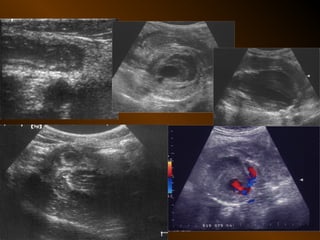

SIÊU ÂM : phụ thuộc người thực hiện

và tình trạng bệnh nhân

Kỹ thuật : chuẩn bị bệnh nhân ?

tần số đầu dò ?

Cách phân tích: dấu hiệu dương tính và âm tính

Chỉ định : linh động

SIÊU ÂM DOPPLER